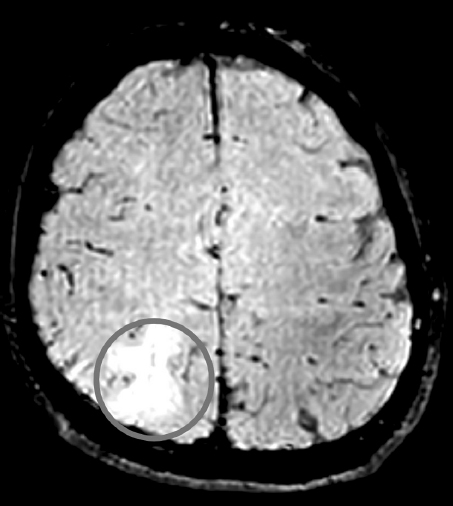

МРТ головного мозга была выполнена 19 пациентам исследуемых групп (8 пациентам группы 1, 2 — группы 2, 9 — группы 3), в том числе с использованием последовательностей SWI/SWAN. Диффузных микрокровоизлияний в веществе головного мозга обнаружено не было, что подтвердило наличие у всех пациентов легкой ЧМТ (рис. 4, 5).

Рис. 5. МРТ головного мозга в режиме SWI/SWAN пациента с сотрясением головного мозга. Диффузных микрокровоизлияний не обнаружено

Fig. 5. MRI of the brain in SWI/SWAN mode of a patient with a concussion. No diffuse microbleeds were detected

Выполнение МРТ головного мозга пациентам, подвергшимся воздействию взрыва, часто невозможно из-за наличия у них металлических осколков в теле. МРТ выполнялась на томографе с напряженностью магнитного поля 1,5Т. Возможно, относительно низкая разрешающая способность по сравнению с томографом 3Т послужила причиной недиагностированных диффузных микрокровоизлияний в веществе головного мозга у пациентов с легкой ЧМТ вследствие воздействия взрыва. Однако отсутствие изменений по данным МРТ, в том числе с использованием импульсной последовательности SWI/SWAN (взвешенной по магнитной восприимчивости), может свидетельствовать и о наличии протекторных свойств средств индивидуальной бронезащиты (шлема) при воздействии на организм факторов взрыва.